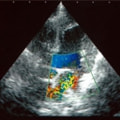

C:超音波写真 僧帽弁逆流と左室流出路狭窄

1年ほど前より左側胸壁からLevine 3/6の心雑音が聴取されていた。雑音の精査のため、心エコー検査を行ったところ、左室流出路の狭窄を伴う肥大型心筋症(閉塞型肥大型心筋症)と判明した。心室の拡張性を上げるため、βブロッカーであるカルベジロールを用いた治療を行っている。肥大型心筋症は犬の心疾患のように、心拡大を認めないことも多く、レントゲン写真のみで心疾患の有無を判断する事が出来ない。また、閉塞を伴わない肥大型心筋症と異なり、閉塞型の本疾患の治療に対し、Caチャネルブロッカーは推奨されない。